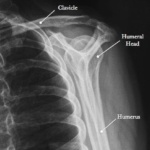

Las radiografías, generalmente llamadas rayos X, producen imágenes como sombras de huesos y ciertos órganos y tejidos. Las radiografías son muy buenas para detectar problemas óseos. Pueden mostrar algunos órganos y tejidos blandos; sin embargo, la MRI y la CT suelen crear mejores imágenes de los mismos. Aun así, las radiografías son rápidas, fáciles de obtener y menos costosas que los otros estudios, por lo que se pueden usar para obtener información rápidamente.

Un tubo especial dentro de la máquina de rayos X emite un haz de radiación controlada. Los tejidos del cuerpo absorben o bloquean la radiación en diferentes grados. Los tejidos densos como los huesos bloquean la mayor parte de la radiación, pero los tejidos blandos, como la grasa o los músculos, bloquean menos radiación. Después de pasar por el cuerpo, el haz alcanza una pieza de un fragmento de película o un detector especial. Los tejidos que bloquean altas cantidades de radiación, como los huesos, aparecen como áreas blancas en un fondo negro. Los tejidos blandos bloquean menos radiación y aparecen en tonos de gris. Los órganos que contienen principalmente aire (como los pulmones) aparecen en negro. Los tumores son por lo general más densos que el tejido que los rodea, por lo que suelen verse en tonos grises más claros.